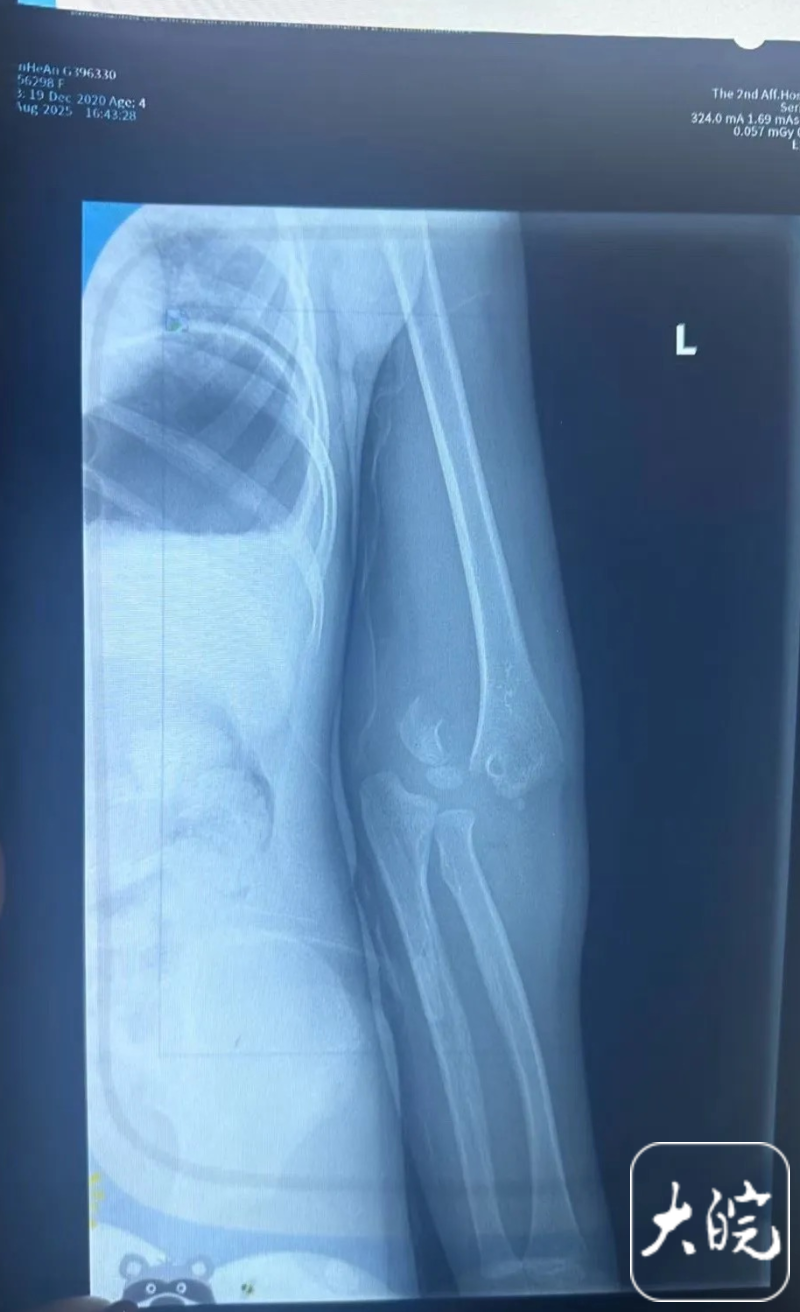

随后陈先生也向记者展示了孩子入院后的诊断报告,“左侧肱骨远端见骨质连续性中断,可见骨折线影,断端稍分离,远端软组织内可见碎骨片影。”陈先生告诉记者,目前孩子已经完成手术,“这两天也在和儿童乐园方面协商解决此事。”